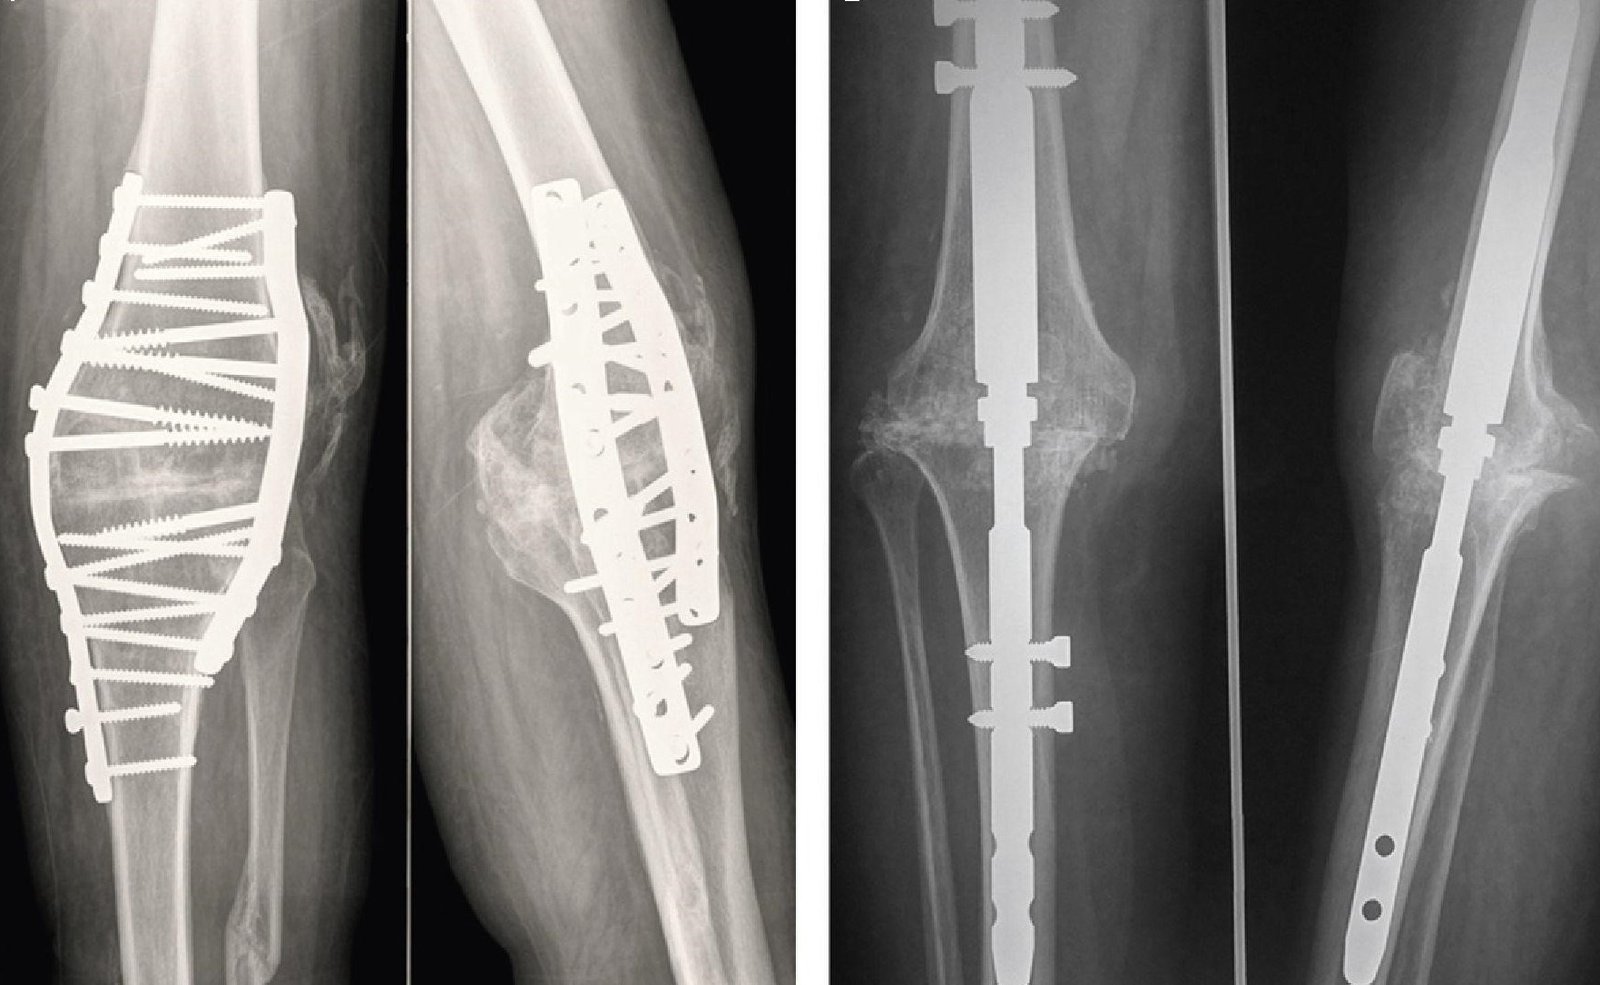

جراحة تثبيت المفاصل بصفة عامة هي دمج العظام ببعضها البعض لتكوين عظمة واحده صلبة. ويتم هذا الدمج باستخدام شرائح ومسامير نخاعية، وفي حالة تثبيت أو إيثاق مفصل الركبة، يتم دمج عظمتي الفخذ والساق (الظنبوب) مما يٌفقد المفصل قدرته على الانثناء بشكل كامل. ولكن ورغم فقدان مفصل الركبة لأحد أهم وظائفه وهي الثني إلا أن هذه الجراحة تُشكل أملاً في بعض الحالات الطبية القليلة.

وتختلف طرق إجراء هذه الجراحة باختلاف تشخيص الإصابة وحالة العظام والأنسجة الرخوة المحيطة بها، وأيضًا الحالة الصحية العامة للمريض. فقد يقوم الطبيب حسب الحالة المرضية، بتثبيت المفصل داخليًا عن طريق المسامير النخاعية اوالشرائح، أو عن طريق التثبيت الخارجي باستخدام مثبتات خارجيه مثل جهاز اليزاروف.

يقوم جراح العظام بإزالة الغضروف والعظام التالفة من أطراف عظام الساق والفخذ، وربطهما باستخدام الصفائح المعدنية أو المسامير، او المثبت الخارجي لتثبيت العظام في مكانها.

يتم تثبيت أو إيثاق مفصل الركبة عن طريق دمج عظمتي الفخذ والساق لتكوين عظمة واحدة. ويتم هذا التثبيت داخليًا باستخدام القضبان والشرائح والمسامير المعدنية، أو خارجيًا باستخدام المثبتات الخارجية.